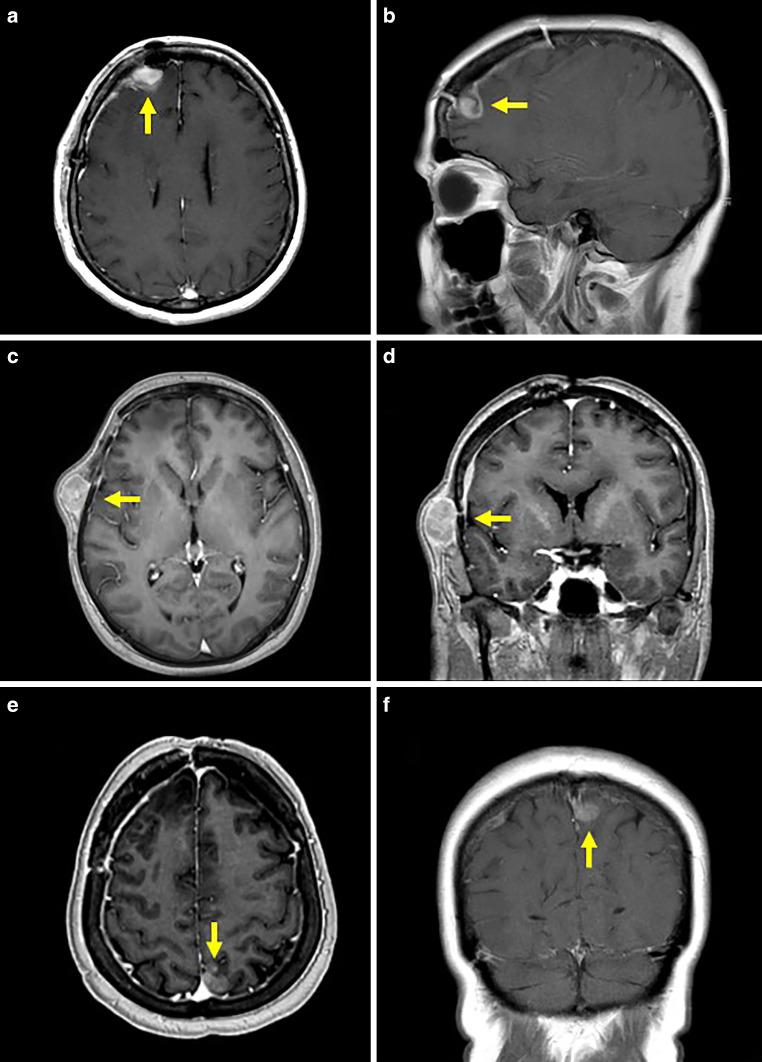

We conducted a systematic literature review in the PubMed database and complemented the data by inclusion of a case treated in our clinic. In this context, we report on a 60-year-old woman with a right frontal glioblastoma, IDH wildtype, MGMT methylated.

Six months after initial diagnosis and primary treatment, there was extensive local intracranial progression with additional extension into the subcutaneous and frontotemporal cranial bones. Despite continuation of multimodal treatment, further extracerebral manifestations occurred 11 months after the initial diagnosis, both in the cranial bone as well as metastases in the right parotid gland, cervical lymph nodes, and lungs. While local radiotherapy enabled the cerebral lesions to be controlled, the patient's clinical condition deteriorated rapidly despite simultaneous systemic therapy. The treatment had to be discontinued, and the patient died 5 weeks after confirmation of the multilocal extracerebral manifestations and a total of 12 months after initial diagnosis.

初次诊断和初次治疗6个月后,颅内出现广泛的局部进展,并进一步扩展至皮下和额颞颅骨。尽管继续进行多模式治疗,但初次诊断11个月后出现了更多的脑外表现,包括颅骨以及右侧腮腺、颈部淋巴结和肺部的转移。虽然局部放疗使脑部病变得到控制,但尽管同时进行了全身治疗,患者的临床状况仍迅速恶化。治疗不得不中断,患者在确认多部位脑外表现后5周死亡,初次诊断后共计12个月。